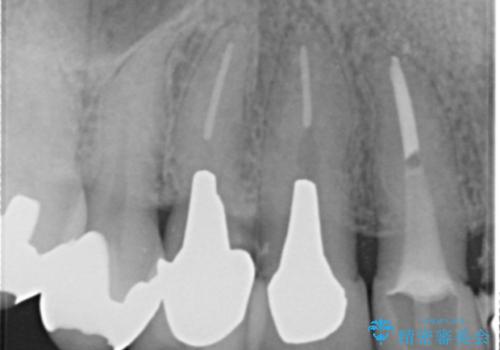

- 若い時に作った前歯のブリッジがの根元が黒くなってきているとのことで来院。

支える歯が1本虫歯がひどく、割れていました。

根の治療からやり直して新しいブリッジにしています。

ブリッジの支台歯は、根の再治療を含めて行なっています。